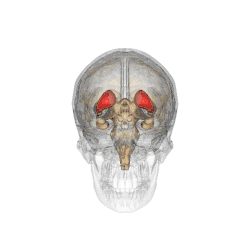

![]() Caudate nucleus (in red) shown within the brain | |

The caudate nucleus is one of the structures that make up the corpus striatum, which is part of the basal ganglia in the human brain.[1] Although the caudate nucleus has long been associated with motor processes because of its relation to Parkinson's disease and Huntington's disease,[2][3] it also plays important roles in nonmotor functions, such as procedural learning,[2] associative learning,[4] and inhibitory control of action.[5] The caudate is also one of the brain structures that compose the reward system, and it functions as part of the cortico-basal ganglia-thalamo-cortical loop.[1]

The caudate nuclei are near the center of the brain, sitting astride the thalamus. There is a caudate nucleus in each hemisphere of the brain. Each nucleus is C-shaped, with a wider "head" (caput in Latin) at the front, tapering to a "body" (corpus) and a "tail" (cauda). Sometimes a part of the caudate nucleus is called the "knee" (genu).[6] The caudate head receives its blood supply from the lenticulostriate artery; the tail of the caudate receives its blood supply from the anterior choroidal artery.[7]